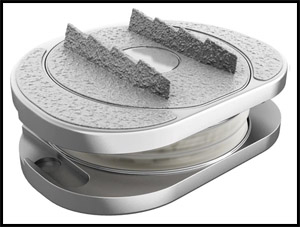

В настоящее время наиболее современным заменителем диска является искусственный диск. Наиболее близким по строению и функции к обычному диску является искусственный диск «М6-С». (Рис.5) Так же как и настоящий диск указанный имплант состоит 2-х частей: искусственного ядра, обеспечивающего осевое сжатие, и кольца из волокнистого материала, обеспечивающего подвижность с контролируемой амплитудой и с шестью степенями свободы. (Рис.6) Такая конструкция обеспечивает физиологическую подвижность позвоночно-двигательного сегмента и предотвращает дальнейшую дегенерацию дисков на уровне соседних позвонков. Биомеханические испытания искусственного диска М6-С подтвердили качество подвижности, эквивалентное человеческому диску.

| Рис.5. Искусственный диск М6-С. | Рис. 6. Устройство искусственного диска М6-С. |